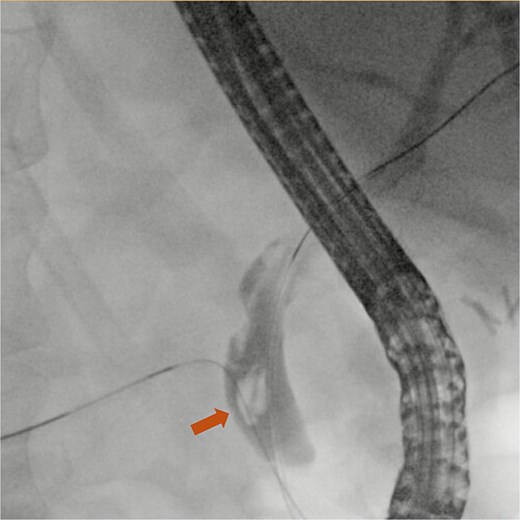

Contrast-enhanced abdominal computed tomography (CT) scan revealed a surgically absent gallbladder. A surgical clip was identified in the region of the ampulla of Vater, and a 4 mm stone was located in the distal common bile duct just proximal to the ampulla (Fig. 1). Subsequently, ERCP was performed, during which a 6 mm brown pigment stone was identified in the middle third of the main bile duct. In addition, a metallic foreign object resembling a surgical clip was noted within the stone (Fig. 2). Biliary sphincterotomy was performed using a traction sphincterotome and electrocautery. The biliary tree was then swept with a 15 mm balloon starting at the bifurcation, and the sludge was removed from the duct. The stone was successfully retrieved using Roth Net (Fig. 3), and a plastic stent was placed in the ventral pancreatic duct. The patient’s liver function test results improved following the procedure, and the patient was discharged. Passage of the pancreatic duct stent was confirmed by abdominal radiography.

ERCP fluoroscopy image showing a common bile duct stone (arrow).